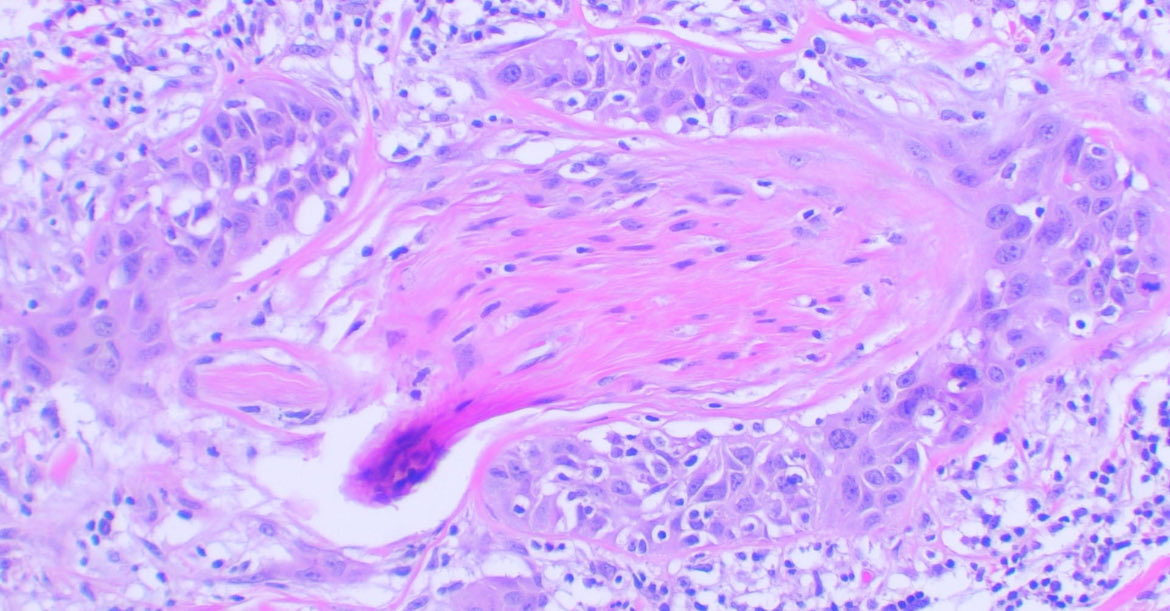

Cutaneous Squamous cell carcinoma Perineural invasion 😢 #path #dermpath #pathology #cancer